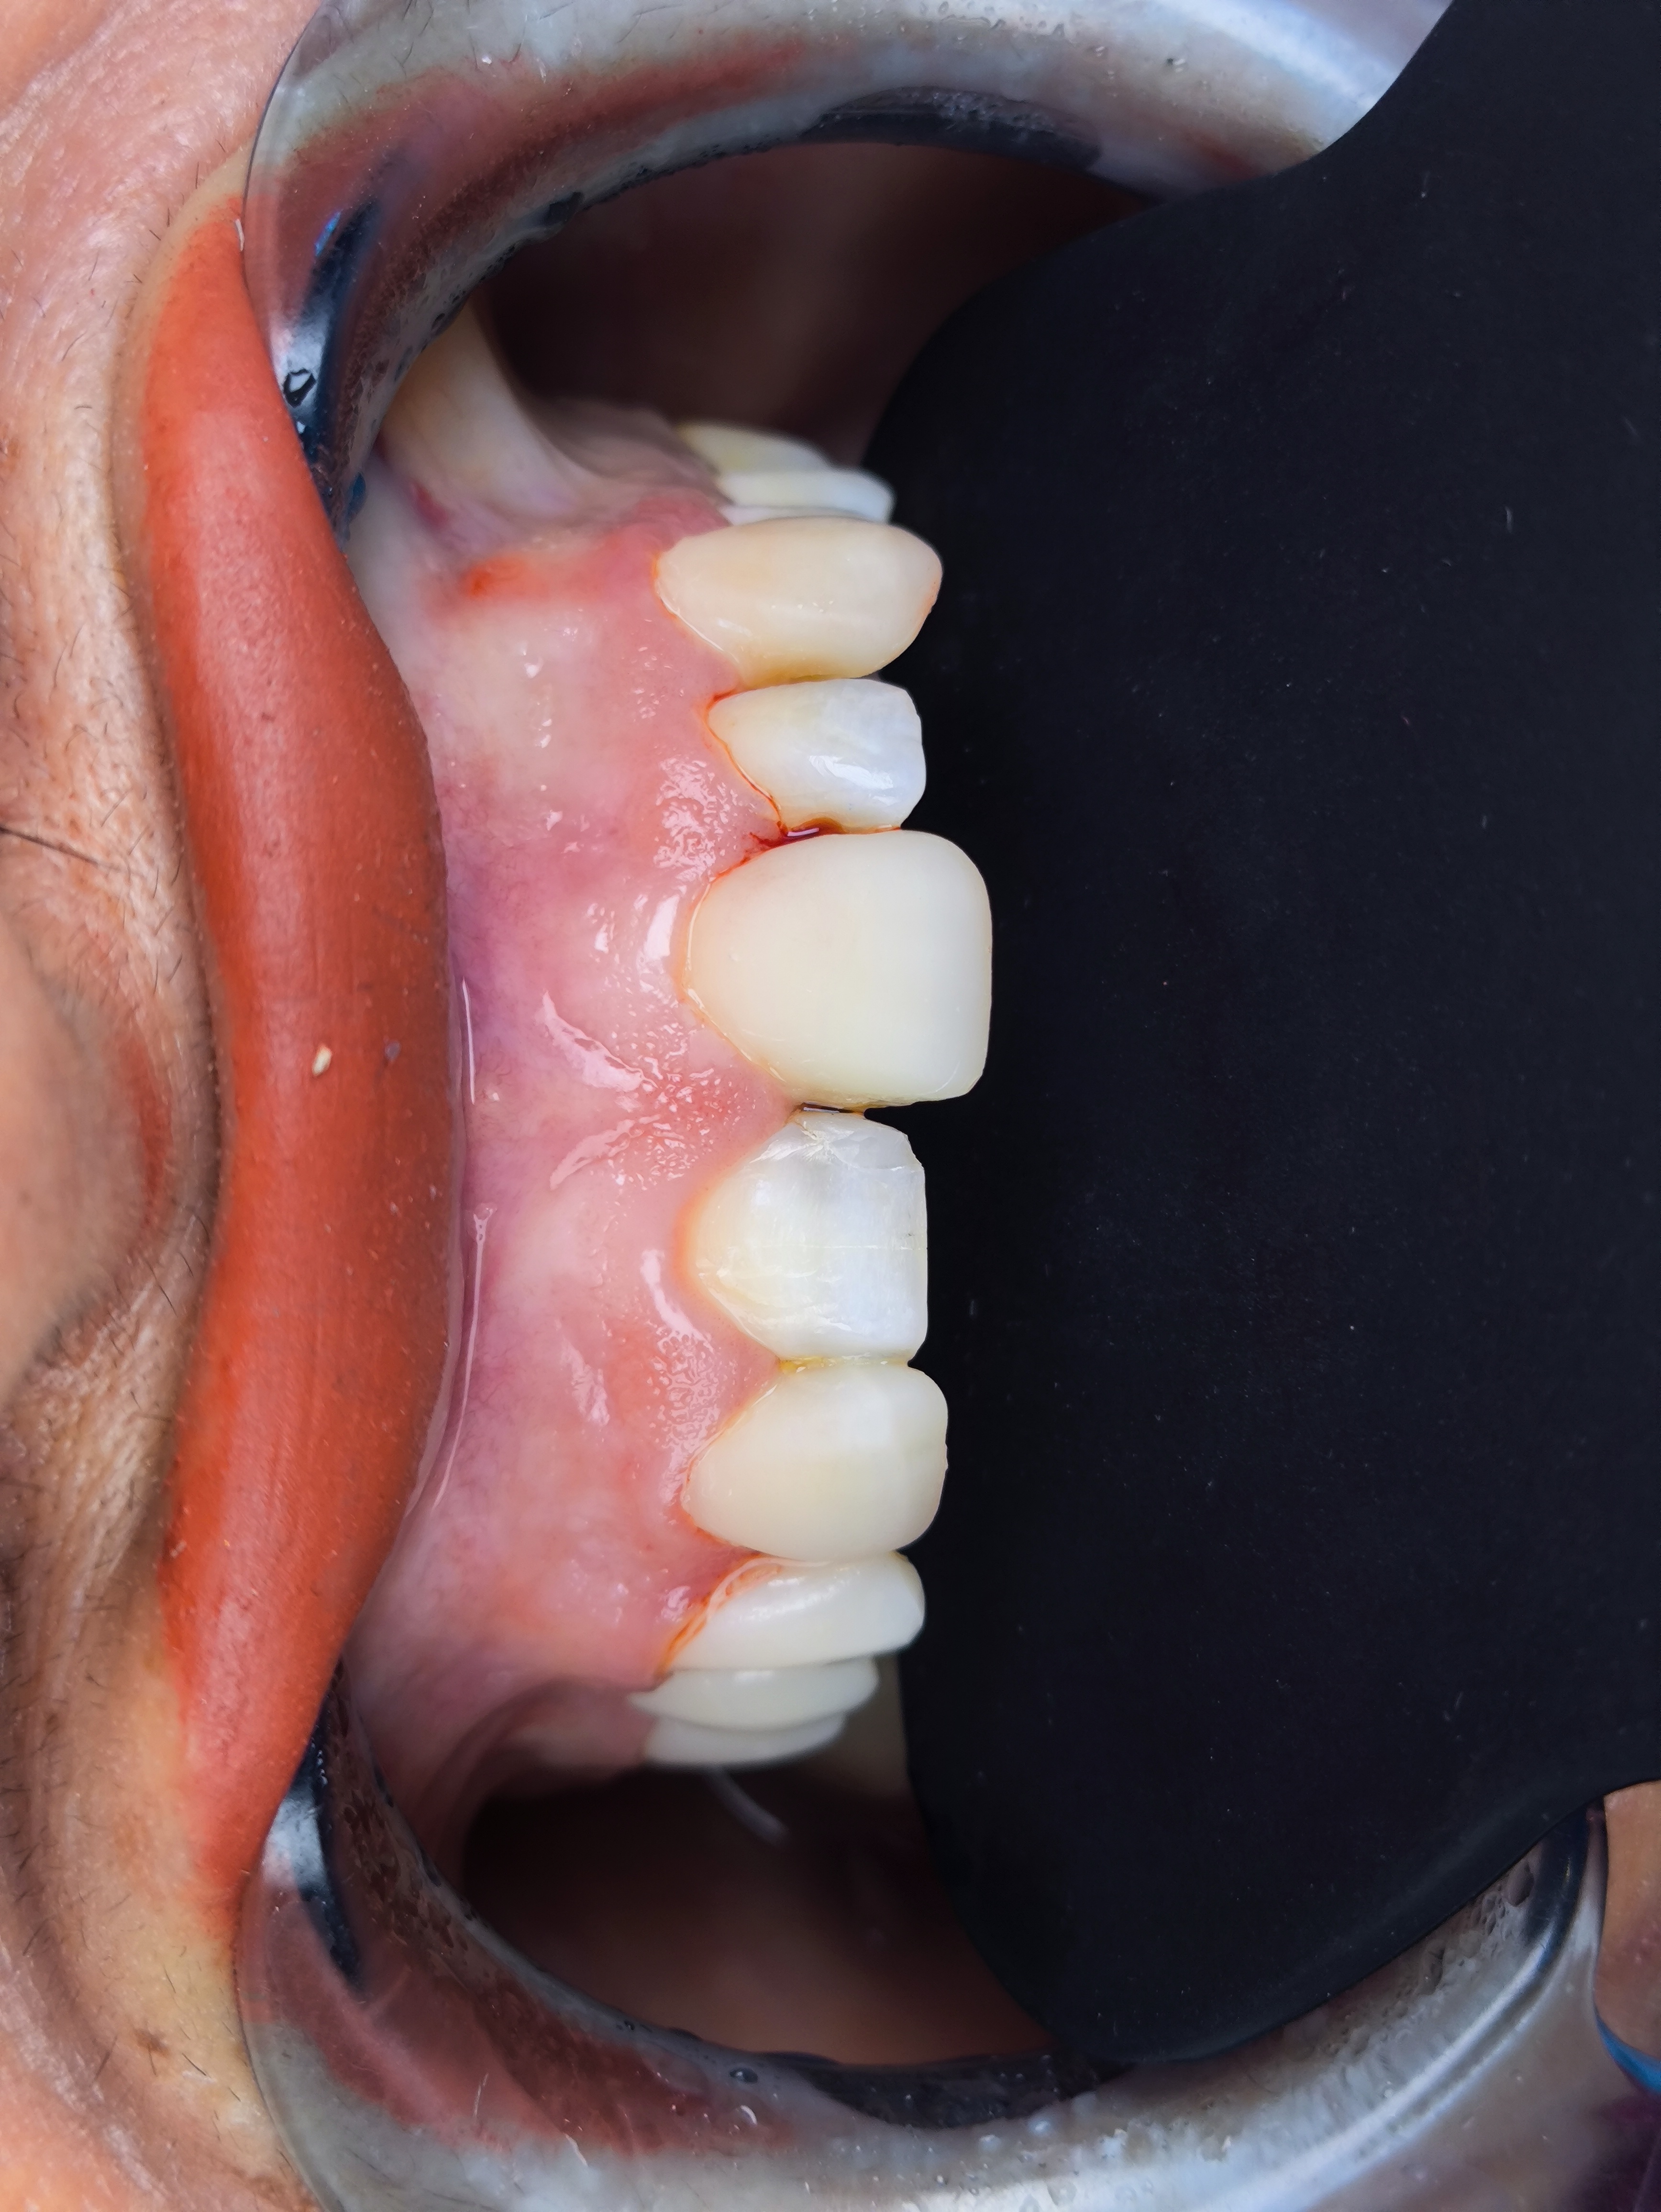

Smile Design Case 1